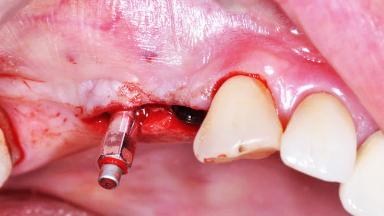

Surgical treatment of a 68-year-old female patient who experienced failure of her conventional bridge in the right maxilla. After removal of the compromised abutment teeth and a healing period of 6 weeks, a sinus floor elevation procedure using the lateral window technique and a composite graft to correct the insufficient bone height is carried out.

Two dental implants are placed in the same surgical session. The case concludes with the presentation of the final fixed dental prosthesis with a distal cantilever unit.